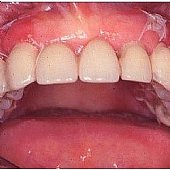

Bilder: Gesamtsanierung

• Provisorische Versorgung des Oberkiefers nach Extraktion in einem Seitenzahnbereich. Deutlich ist der Weichgewebs-Effekt zu den Zähnen im Seitenzahnbereich zu erkennen.

• Provisorische Versorgung des Oberkiefers nach Zahnfleisch-Transplantation. Die Defekte sind verschwunden und ausgeglichen.